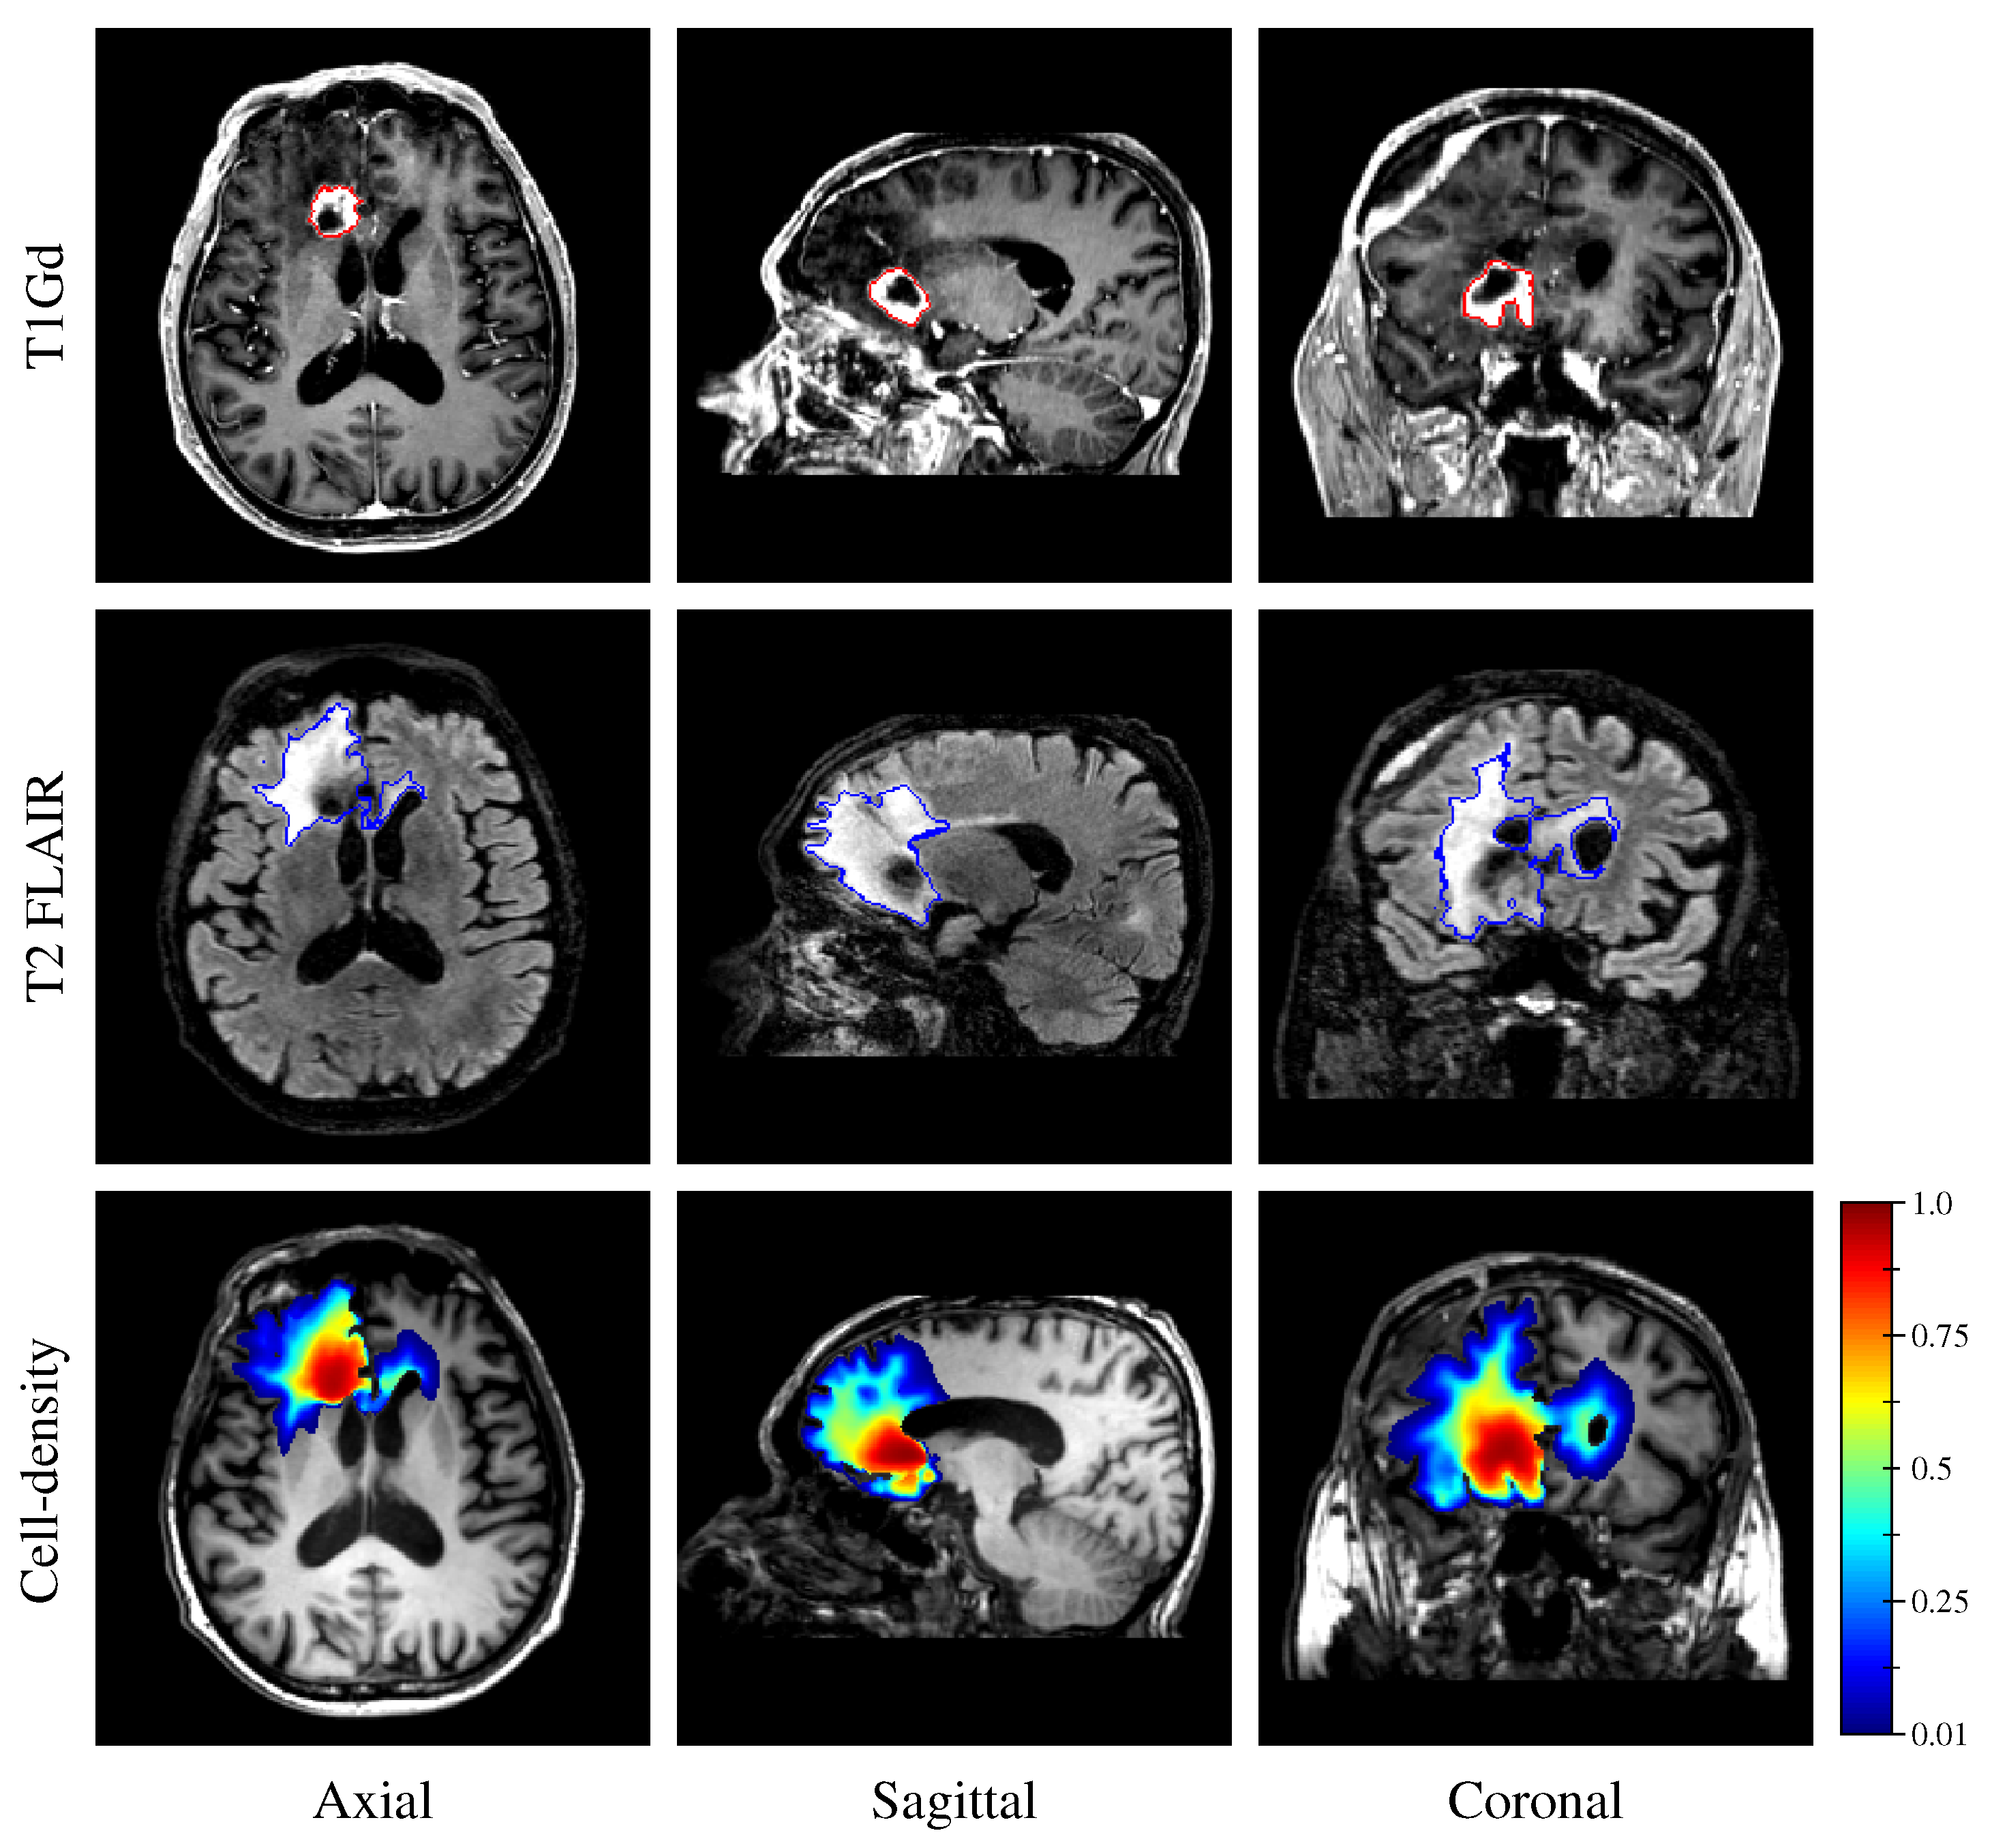

Finally, to demonstrate the applicability of our approach in a clinical context, a cell-density map was generated from the retrospective MR data of the GBM patient (see Section 2.2 and Section 2.3). To this extent, the segmented enhancing core and edema regions (see Section 2.3.5) were provided to the first network along with the derived unit tumor cell diffusion tensor.

Finally, the estimated tumor cell-density distribution for the studied GBM patient provided by the first network (see Figure 5) is depicted in Figure 12 along with the T1Gd and T2 FLAIR images with superimposed segmented enhancing core and edema contours, respectively.

The proposed method was found to provide accurate estimations of the three-dimensional tumor cell distribution from only two imaging contours at a single time point, with a median voxelwise MAE below 10−2 within the c > 0.01 contour—as evaluated on 200 synthetic tumors grown over the real brain domain of a test subject not used for network training. Our method also provided accurate estimates of the individual diffusion and proliferation parameters of the model from three imaging contours extracted from two time points for the same test tumors, with median relative errors of 5.86% and 2.75%, respectively (see Figure 10), and strong concordance ( CCC 0.95 ) with the true parameter values (see Figure 11). Furthermore, we showed that the spatio-temporal evolution of the tumor cell-density distribution at later time points (90 d and 180 d later) can be accurately captured from the estimated distribution at imaging time and parameter values using the reaction-diffusion model. The ASSD between the true and estimated imaging contours obtained for threshold values of c 1 = 0.80 and c 2 = 0.16 were indeed found to be lower than or equal to the pixel spacing ( 1 m m × 1 m m × 1 m m ) in most cases (see Figure 8). Nevertheless, a loss of accuracy in the estimated tumor cell-density over simulated time was observed (see Figure 7, Figure 8 and Figure 9 and Table 3), imputed to the amplification of errors originating from uncertainties in the estimated model parameter values and tumor cell-density distribution at imaging time. In particular, artefactual local maxima in the tumor cell-density distributions predicted by the CNN were found to give rise to new tumor foci over time. Post-processing steps were introduced to circumvent these effects (see Section 2.6), but residual artefacts were still observed, resulting in a large Hausdorff distance though small ASSD values for a few isolated cases (see outliers in Figure 8a,b). Our approach was also found to be robust to uncertainties in the tumor cell-density threshold values defining the input imaging contours of both CNNs. Indeed, all combinations of ± 10 % perturbations on both threshold values used to generate the contours resulted in an increase in median relative error within reasonable ranges of 14.82–22.39% and 10.25–17.79% for the diffusivity and proliferation rate, respectively. Finally, we also demonstrated the applicability of our proposed method to actual MR data of a GBM patient, for which we were able to reconstruct a tumor cell-density distribution compatible with the imaging data. Nevertheless, the lack of biopsy samples combined with the multiple treatments undergone by the patient prevented the validation of the estimated distribution, which was left for a future prospective study.